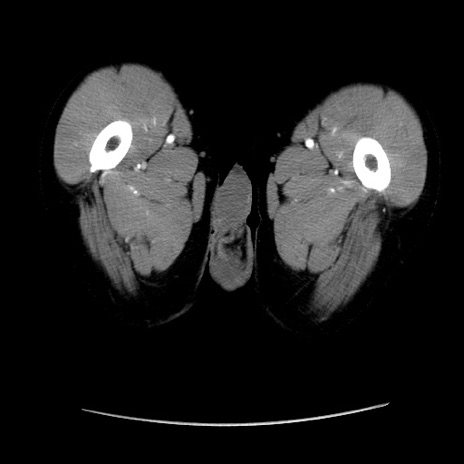

症例37(横断像)

【症例】40歳代 男性

【主訴】腹痛

【現病歴】4時間ほど前に電車に乗車中に臍部上より腹痛出現。徐々に増悪し起立困難となり、救急外来受診。生ものは数日食べていない。今朝お雑煮を食べた。

【身体所見】BT 36.8℃、BP 117/84mmHg、HR 91/min、SpO2 97%、苦悶様、腹部:臍上部広範囲圧痛あり、反跳痛±

【データ】WBC 8100、CRP 0.03